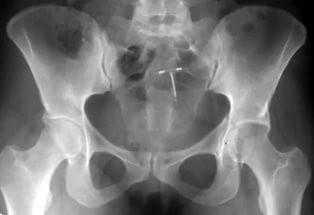

Рентгенография при подозрении перелома костей таза

При всех подозрениях на перелом таза рентгенологическое исследование следует начинать с оценки рентгенограмм таза в переднезадней проекции. Явные линии перелома обычно легко диагностируют. Кроме того, можно локализовать подозрительные на перелом поля и сделать соответствующие снимки в косых проекциях. Для точной диагностики подозреваемых переломов могут потребоваться боковые, аксиальные и переднезадние проекции с наклоном головного конца стола на 35°.